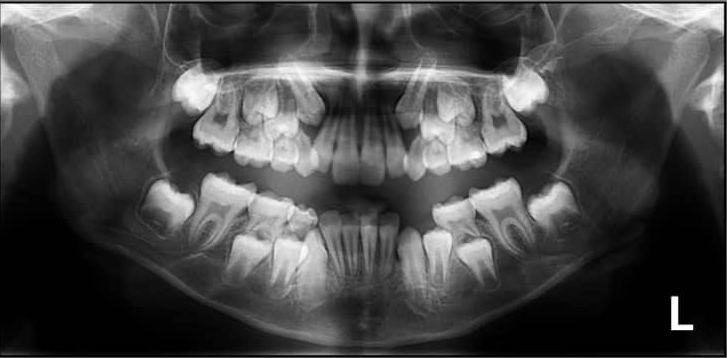

1. How old is the patient with the following X ray?